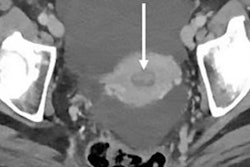

A 56-year-old woman with benign hemangioma. Lesion was originally reported as indeterminate enhancing mass, and outside report recommended biopsy. Classic features of benign hemangioma are shown. Error was attributed to faulty reasoning. (A) Axial MR image obtained five minutes after contrast agent administration shows peripheral nodular discontinuous enhancement. (B) Axial MR image obtained 10 minutes after contrast agent administration shows centripetal progression of enhancement (arrow). (C) Axial fast imaging employing steady-state acquisition (FIESTA) MR image shows lesion is homogeneously hyperintense compared with liver parenchyma. Images and caption courtesy of the ARRS.Kostrubiak and colleagues identified 357 secondary MRI reports for body exams that were originally performed and interpreted at an outside center between January 2015 and December 2018. They compared the original report from the outside facility to the secondary interpretation conducted at the University of Vermont and categorized the cases as "discrepancy" or "no discrepancy." The group then further divided the exams by type of error: perceptive or cognitive.